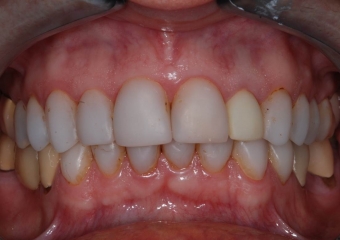

Imagens com facetas e prótese fixa em porcelana sobre implante